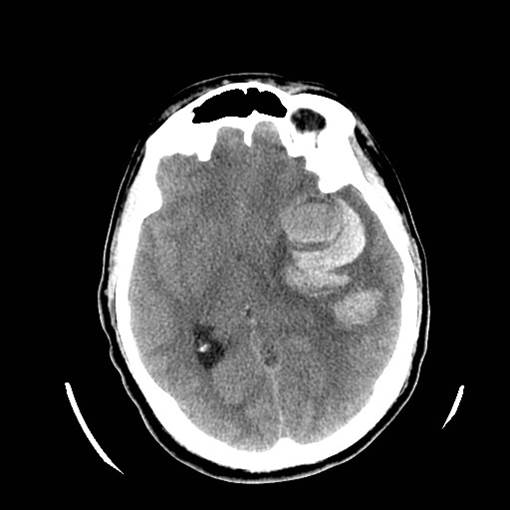

Figure 2: Hemorrhagic Stroke. The images below show a CT scan of a traumatic cerebrovascular injury, with a dissection of the right vertebral artery (left image) and a large stroke and intracerebral hemorrhage with midline shift on the right side of the brain (right image). (Images courtesy of Dr. McMurtrey)